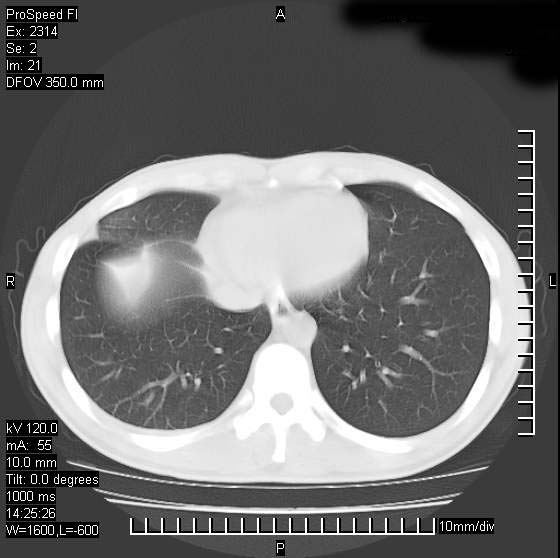

男性,再生障碍性贫血,入院前发热10天,最高40c,右侧胸痛,外院ct示右上,中肺边缘模糊的球性影(就是我现在图中标示的范围),考虑炎症,在我院使用头孢呋辛,洛美沙星10天,高烧消退,自感下午稍有发热,但今天ct示右上,中肺病灶明显扩大,还是考虑炎症,看其中的球型影是否霉菌感染??,是否能排除结核?

右肺中叶外侧段病变,上缘界限不清,下缘锐利,以段性发病为主,内见巨大空洞及空洞内容物,结合病史首先考虑:化脓性肺炎。不除外霉菌感染!

考虑霉菌感染.理由1\\有临床基础疾病,2\\有坏死的空腔,其内可见软组织影.

片状高密度影内见空洞影,内可见球形软组织密度影,并有新月征,考虑霉菌感染.